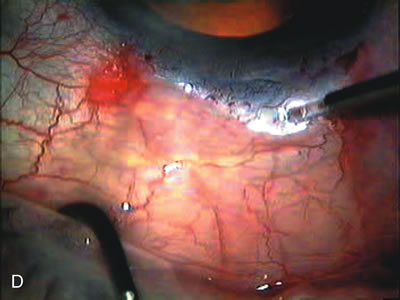

The inflammation associated with lens extraction at any site usually causes complete failure of a marginal functioning bleb. In addition, pressure reduction by medical means is usually minimal in these recalcitrant cases, and combined surgery is indicated. In the past, these cases were approached with large-incision ECCE, clear corneal cataract incision, and bleb revision. Drawbacks included those mentioned earlier for large incision clear corneal cataract extraction, and bleb revision is often associated with conjunctival buttonholes, wound leaks, subconjunctival hematoma, destruction of friable sclera, and associated hypotony. With the advent of modern-day cataract surgery, a phacotrabeculectomy is often possible adjacent to the failed filter (Fig. 7). The ability to combine cataract extraction with implant and filtration surgery all through the same small incision has greatly improved outcomes for patients with marginal preoperative filters. There are several other viable options in this case. If the surgeon elects to remove the cataract through a temporal clear corneal incision, the bleb may be revised or a new adjacent filter fashioned. As mentioned earlier, revising a failed filter is technically challenging. If the surgeon believes it is not feasible to revise the filter or fashion a new one, a glaucoma drainage implant is a reasonable option combined with temporal lens extraction.172

Fig. 7. Phacotrabeculectomy adjacent to a failed filter in cataractous eye. The ability to combine small-incision cataract extraction with trabeculectomy all through the same incision adjacent to the failed filter allows the surgeon to work in a familiar superior area. Avoiding incisions into the existing bleb decreases conjunctival buttonholes, hypotony, operating room time, and subconjunctival bleeding. A. Appearance of failed bleb with exposure of superior temporal quadrant gained with a corneal traction suture. B. Prepare a limbus-based conjunctival flap and a scleral flap. C. This bleb is at high risk to fail again justifying the need for MMC, 0.2 mg/cc applied on a pledget for 4 minutes. D. Insert the keratome and perform phacotrabeculectomy in the usual fashion.